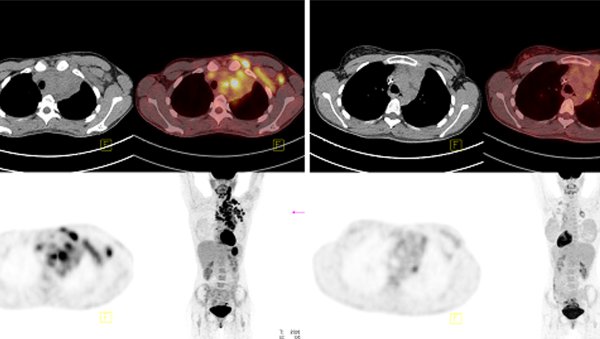

W pracy omówiono wyniki leczenia brentuksymabem vedotin u chorej z wczesnym nawrotem chłoniaka Hodgkina po leczeniu programem BEACOPP eskalowany. Przedstawiono mechanizm działania leku, jego objawy niepożądane oraz miejsce w leczeniu nawrotowych/opornych postaci HL.